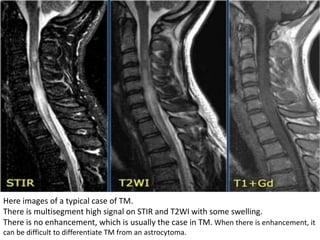

Here images of a typical case of TM.

There is multisegment high signal on STIR and T2WI with some swelling.

There is no enhancement, which is usually the case in TM. When there is enhancement, it

can be difficult to differentiate TM from an astrocytoma.